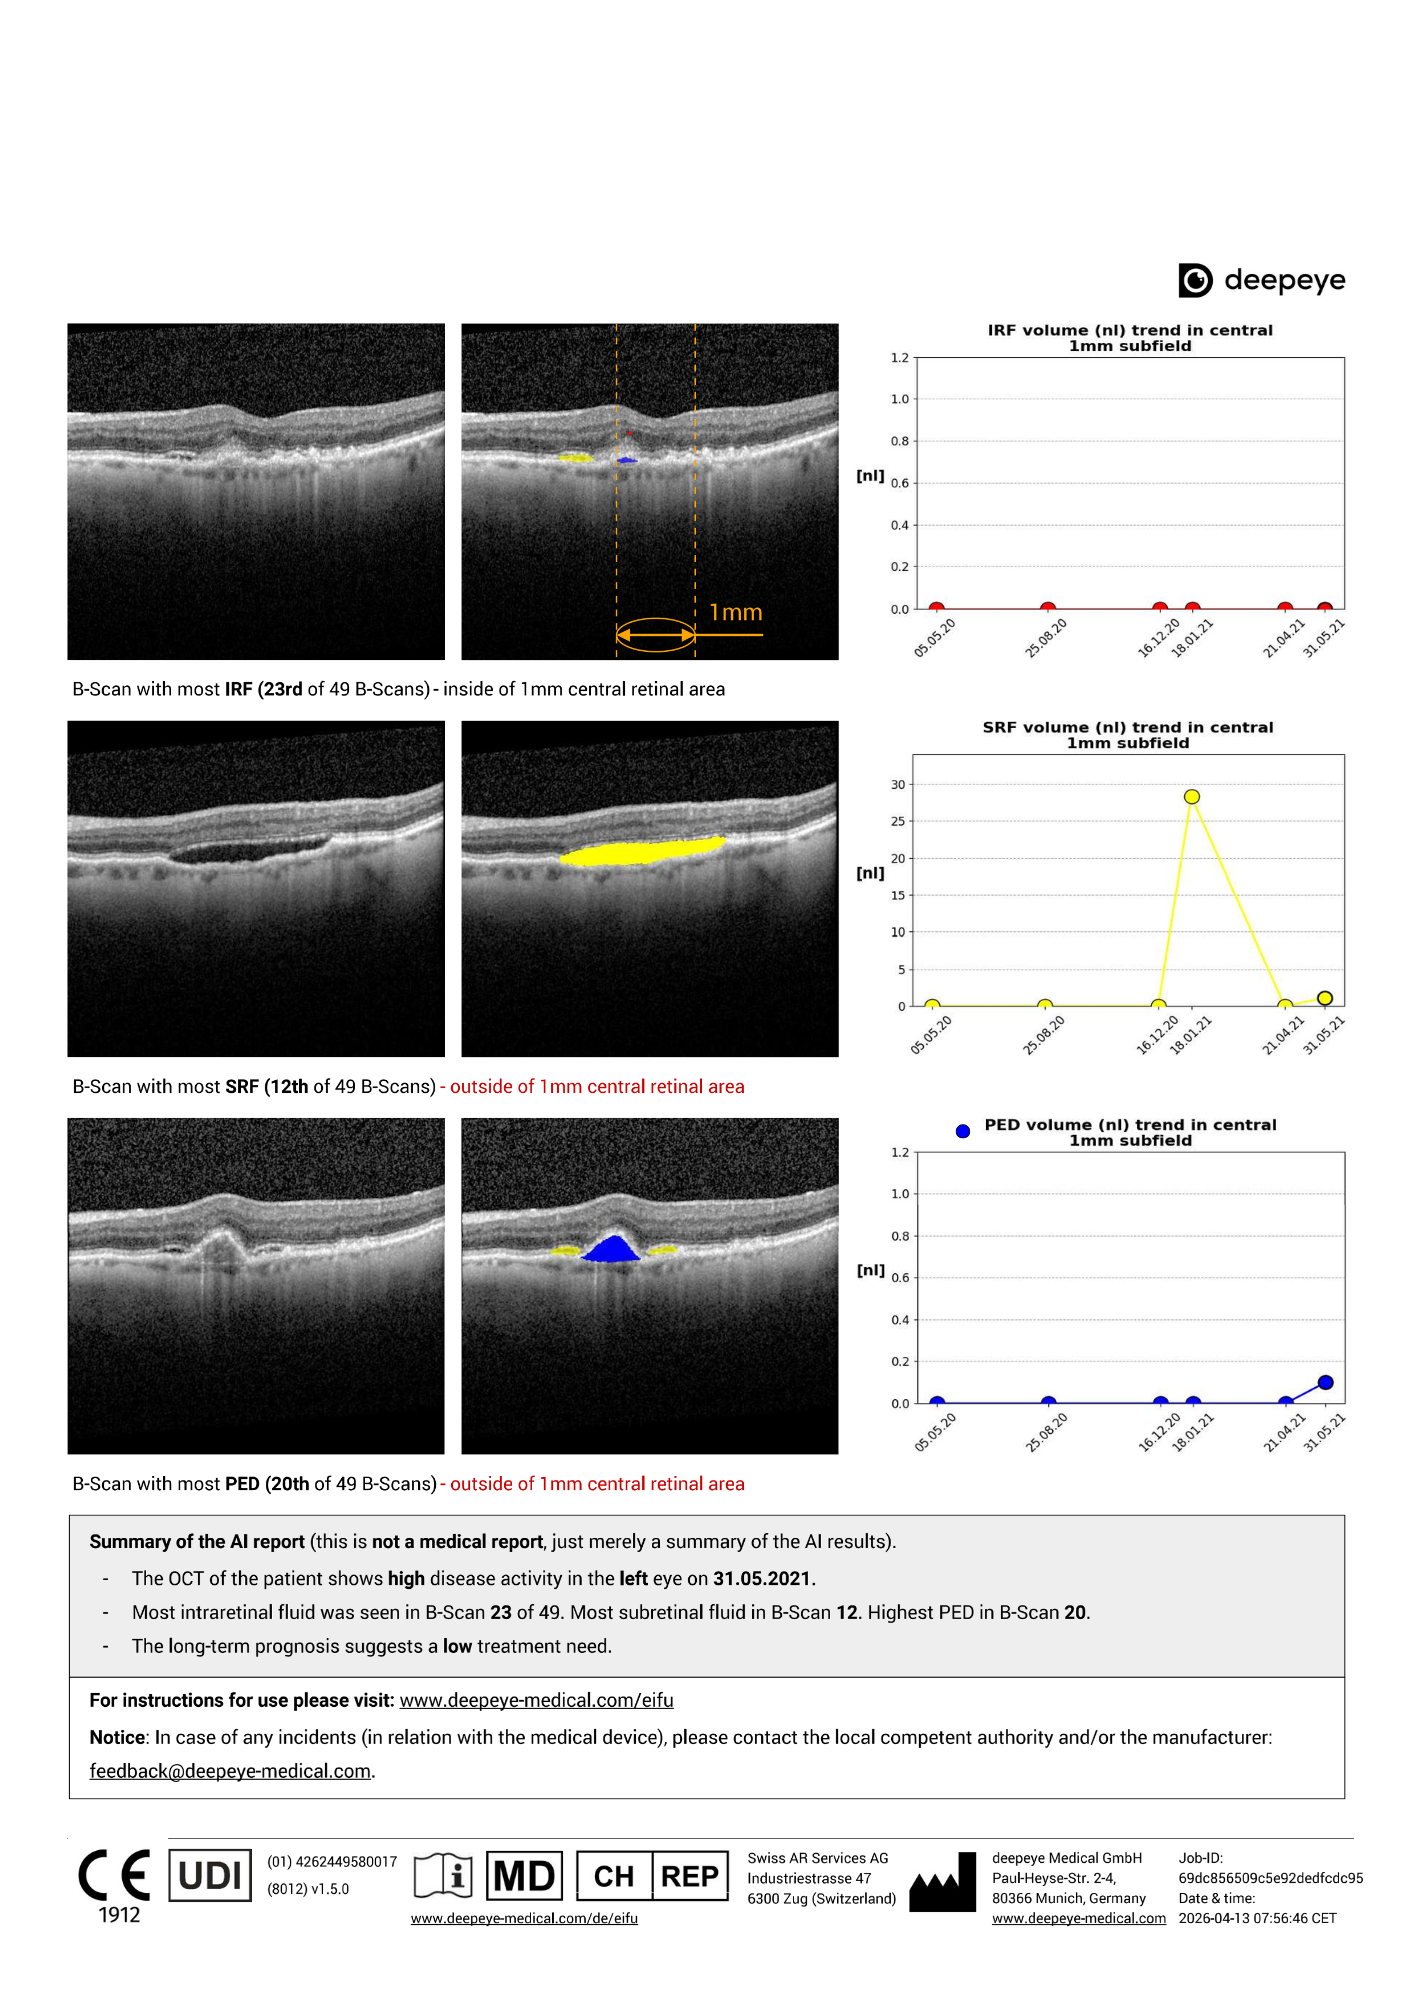

👁️ Explorer un rapport OCT généré par l'IA pour la nAMD

📉 Comprendre l'activité de la maladie en un coup d'œil

🔮 Voir les prédictions de besoin de traitement à long terme.